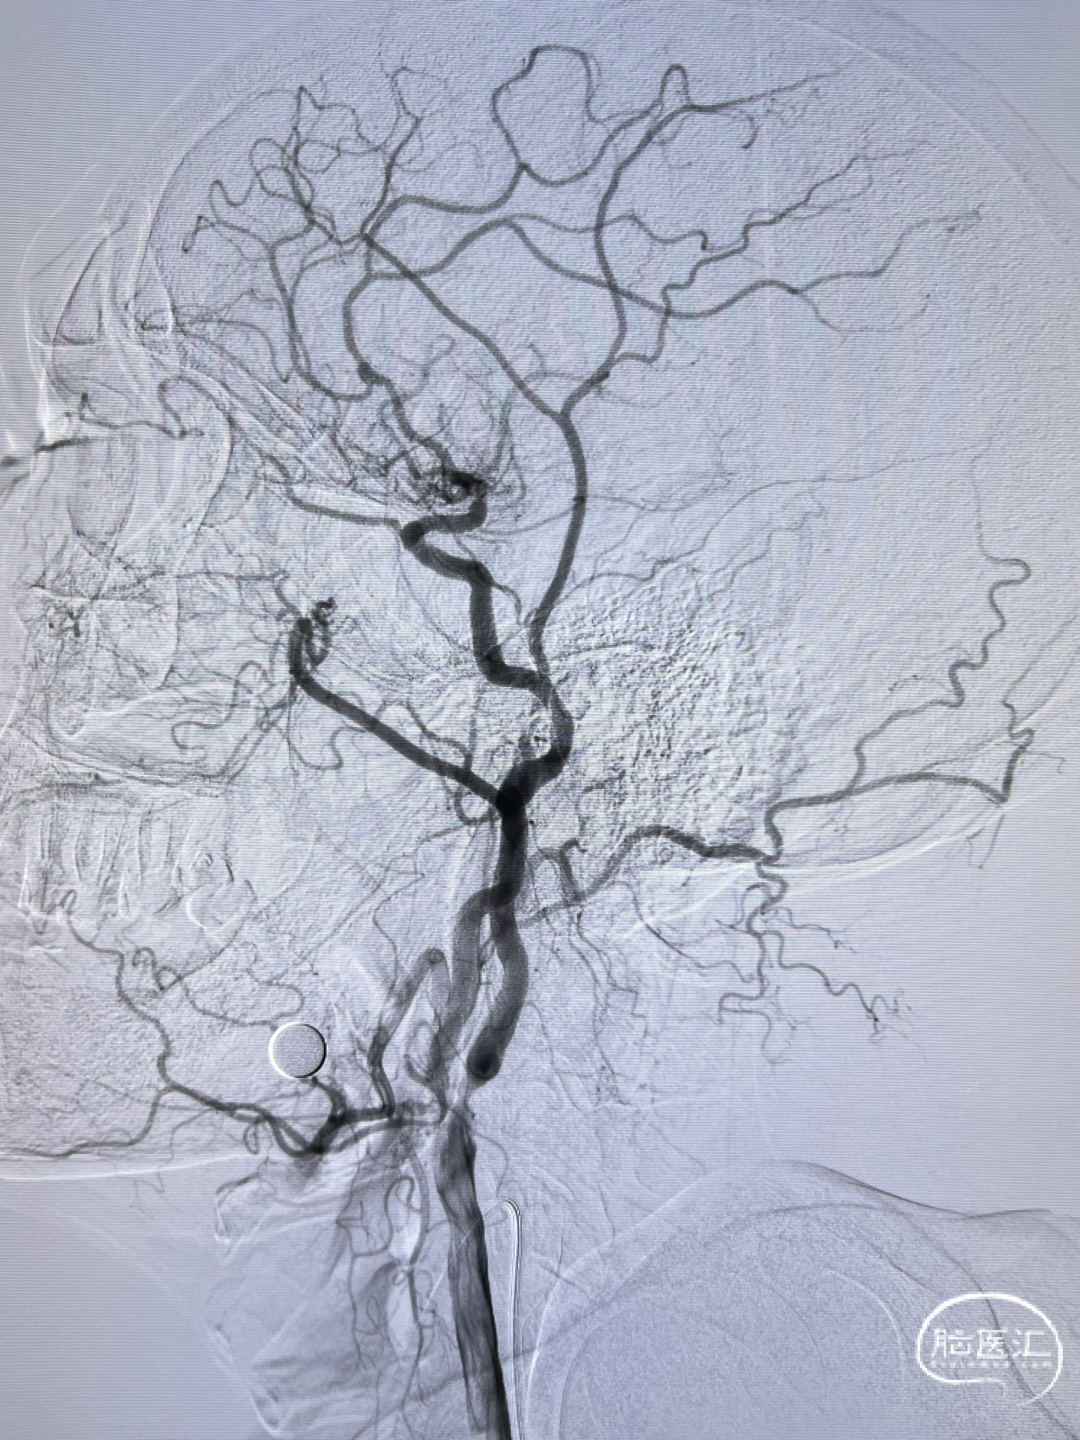

左侧颈内动脉重度狭窄,左侧大脑中动脉闭塞,通过前交通动脉向右侧大脑中动脉供血区代偿。

后循环造影。

左侧颈内动脉正侧位造影,狭窄解除。